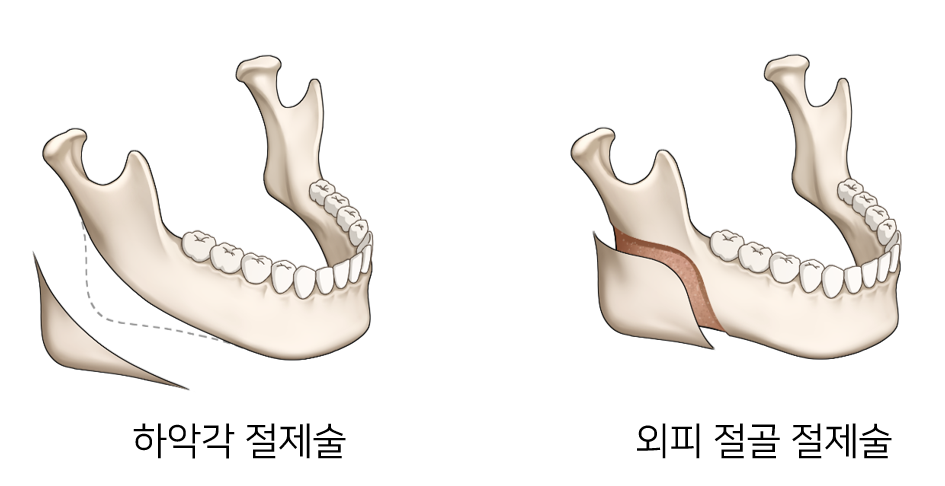

사각턱의 모양에 따라 수술법이 달라지며, 옆에서 보았을 때 튀어나온 턱뼈각을 부드럽게 다듬고, 정면 에서 보아 넓은 부분은 턱뼈의 바깥쪽 피질골을 깎아내는 외피질골 절제술을 시행합니다. 이러한 방법을 통하여 옆뿐만 아니라 정면에서 바라본 얼굴의 모습을 갸름하게 만들어 줍니다.